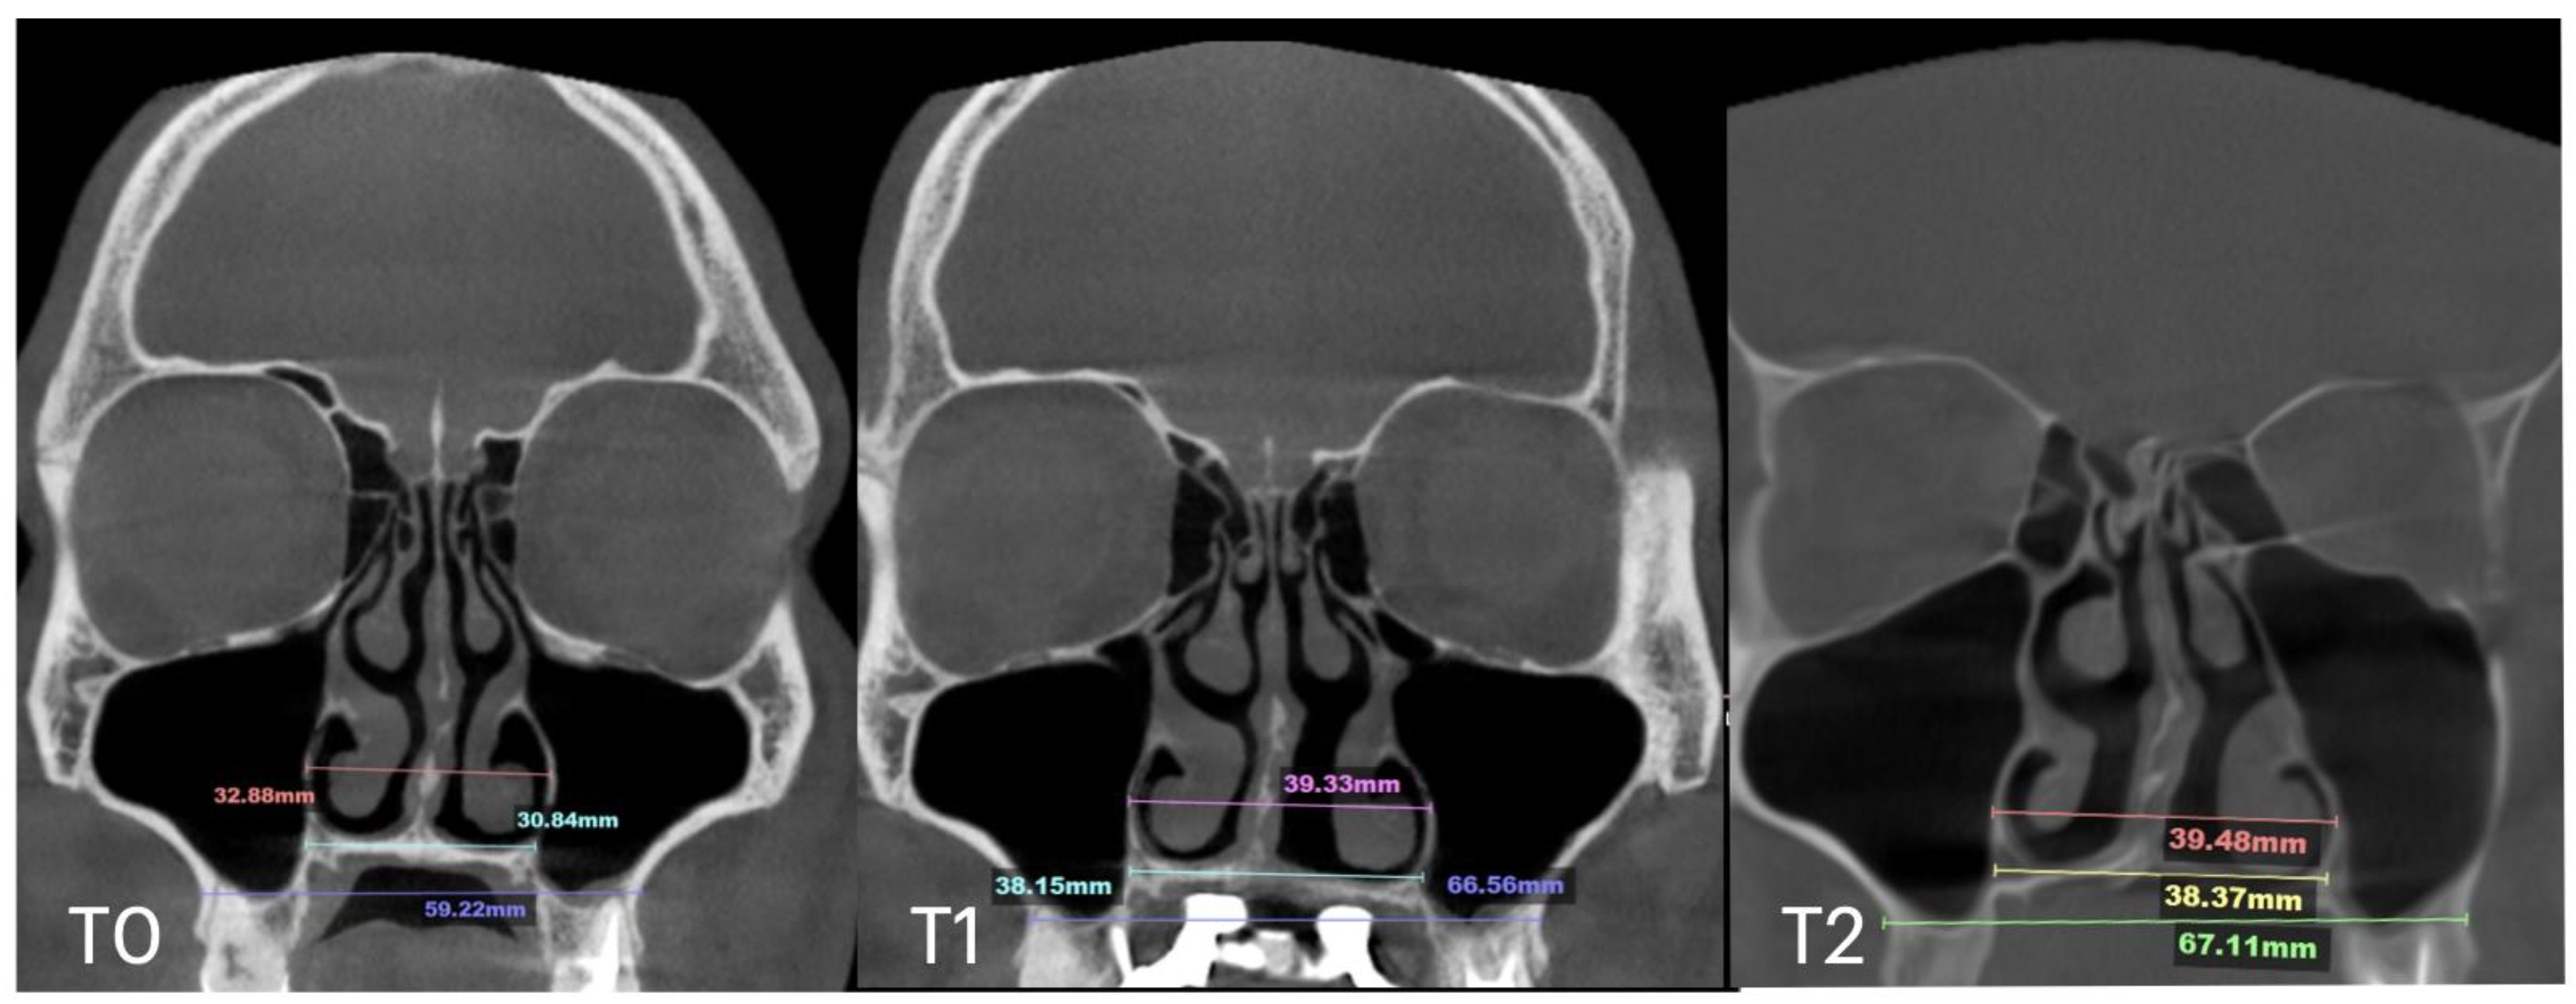

| Nasal Base Width, mm | Maxillary Base Width, mm | Lateral Nasal Width, mm | Inter-Pterygoid Distance, mm | Midpalatal Suture Separation, mm | |||||||||

|---|---|---|---|---|---|---|---|---|---|---|---|---|---|

| T0 | T1 | T2 | T0 | T1 | T2 | T0 | T1 | T2 | T0 | T1 | T2 | T1 | |

| Case A | 30.84 | 38.15 | 38.37 | 59.22 | 66.37 | 67.11 | 32.8 | 39.33 | 39.48 | 28.01 | 32.88 | 33.38 | 10.5 |

| Case B | 30.61 | 34.41 | 34.97 | 59.73 | 63.47 | 60.56 | 31.79 | 34.6 | 35.35 | 29.18 | 31.38 | 34.59 | 5.7 |

| Case C | 28.40 | 38.32 | 36.72 | 53.63 | 62.43 | 59.80 | 31.29 | 38.45 | 38.51 | 29.15 | 35.8 | 35.36 | 8.47 |

| Case D | 26.25 | 33.27 | 31.54 | 55.9 | 61.84 | 60.37 | 33.98 | 35.94 | 38.09 | 29.77 | 29.24 | 29.02 | 6.2 |